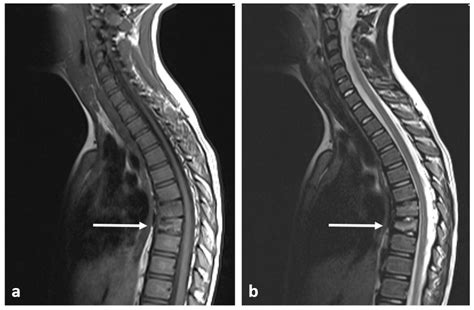

A spinal cord neoplasm is an abnormal growth of cells within or adjacent to the spinal cord. These growths can be classified based on their location: intramedullary (inside the spinal cord substance), extramedullary-intradural (inside the covering of the spinal cord but outside the cord itself), or extradural (outside the spinal cord covering, usually involving the vertebrae). Regardless of the location, these masses exert pressure on the delicate nerve fibers, leading to the clinical manifestations patients experience.

Thoracic (Mid-back) Band-like sensations around the chest or abdomen, leg weakness, gait changes.

Once a physician suspects a spinal cord neoplasm based on the described symptoms, they will utilize advanced imaging to confirm the diagnosis. The goal is to identify the size, exact location, and potential nature of the growth. Magnetic Resonance Imaging (MRI) is the gold standard for evaluating spinal cord tumors because it provides high-resolution images of the spinal cord, nerve roots, and surrounding tissues.

In some cases, your medical team may suggest a contrast-enhanced MRI to better visualize how the tumor interacts with the spinal cord tissues. Additionally, if the symptoms are ambiguous, doctors might conduct an electromyography (EMG) or nerve conduction study to rule out other peripheral nerve conditions that mimic Spinal Cord Neoplasm Symptoms.